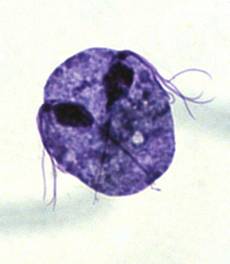

รูปที่ 6 เชื้อพยาธิทริโคโมแนสในช่องคลอดทำให้เกิดตกขาวผิดปกติแบบเป็นฟองและคัน